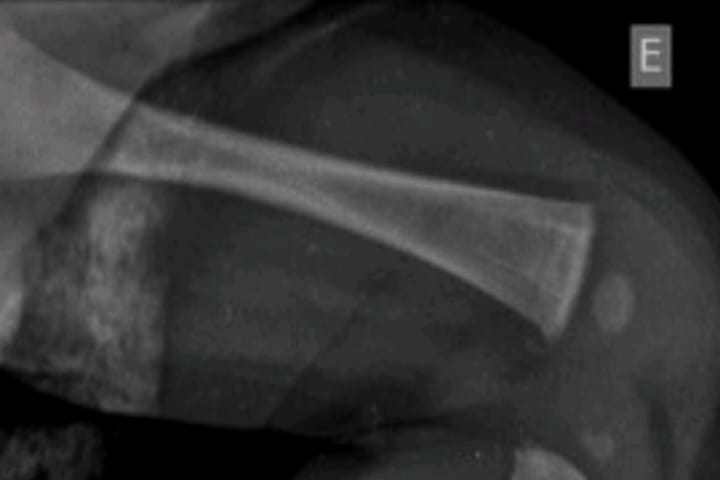

“É uma criança que nem mesmo tem força pra rolar de uma cama e cair no chão, o rosto, a barriga e a perna estavam lesionados, fratura na tíbia antebraço, costelas… pra chegar nesse nível de lesões, as agressões foram intensas”, disse o Delegado.